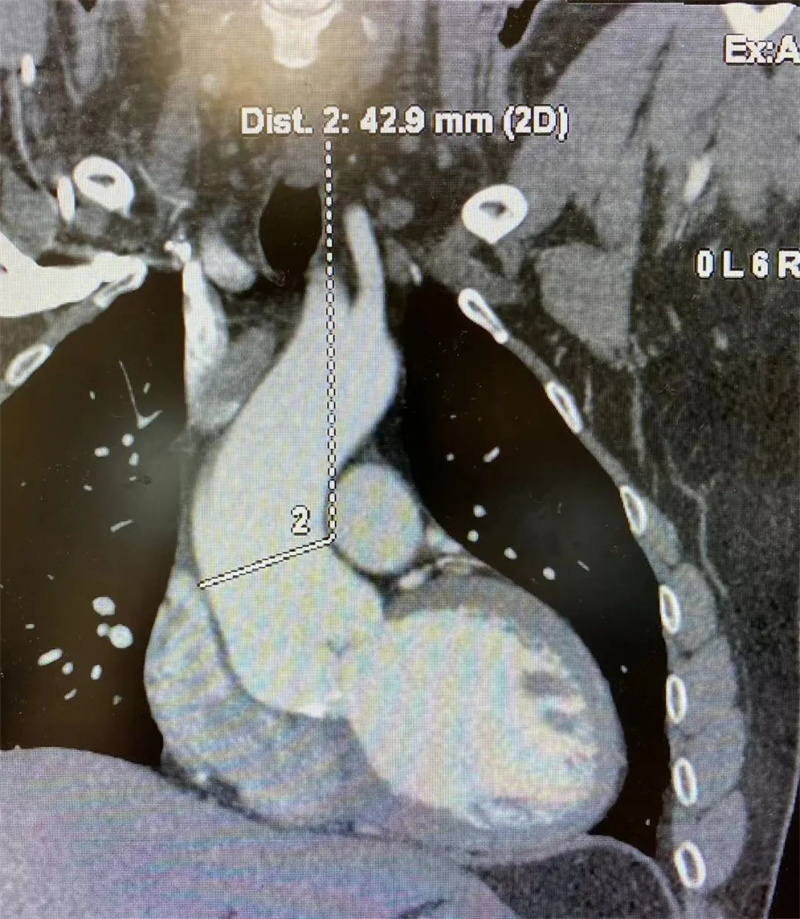

入院心脏彩超显示:小刘主动脉窦部扩张,直径约52mm,升主动脉扩张,直径约43mm,升主动脉壁菲薄如纸,右冠状窦瘤形成且大部分瘤体已脱入室缺,这意味着如不及时治疗,小刘心脏里的“定时炸弹”将随时引爆,而他却不自知。